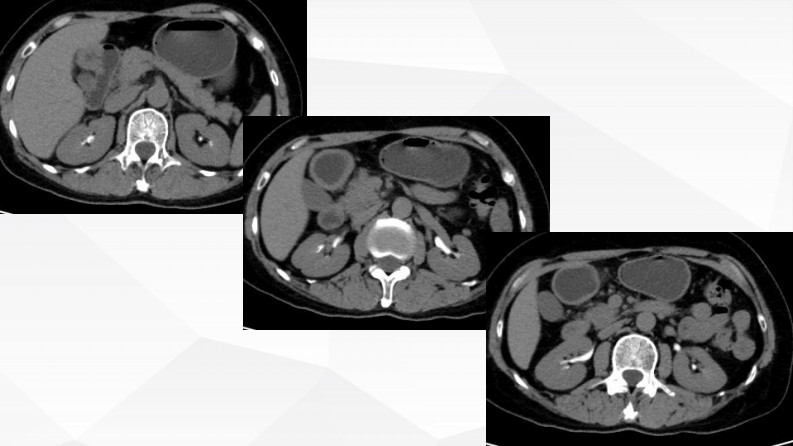

胰腺富血供占位诊断及鉴别诊断--张欢.pdf